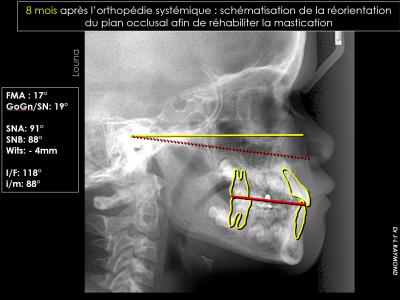

Les classes III par brachymaxillie (les plus fréquentes) sont associées à une bascule du plan d'occlusion maxillaire vers le haut et vers l'avant, identifiable à l'examen de la cinématique mandibulaire : les mouvements sont propulsifs en latéralité.

Leurs prises en charge en orthodontie systémique doivent corriger cette anomalie verticale en retrouvant une cinématique mandibulaire frontale.

Ce traitement a duré 9 mois avec :

- Gouttière Orthopédique Systémique (anciennement Gouttière Orthopédique de Disjonction), constituée de 2 plans en résine scellés au CVI sur les dents latérales, et laissant une infraclusie postérieure permettant l'égression des molaires mandibulaire et la bascule du plan occlusal. Cette GOS possède au niveau palatin un disjoncteur pour réaliser une disjonction maxillaire rapide.

Cette gouttière est progressivement meulée, d'abord en postérieur puis en antérieur afin d'accompagner la bascule du plan occlusal. La GOS sert ainsi de guide à l'installation de la nouvelle cinématique mandibulaire : frontale et symétrique.

- Masque facial (Chronomask) avec port 13h/jour avec élastiques 3/8 14 oz. La traction est orientée vers le bas et vers l'avant.